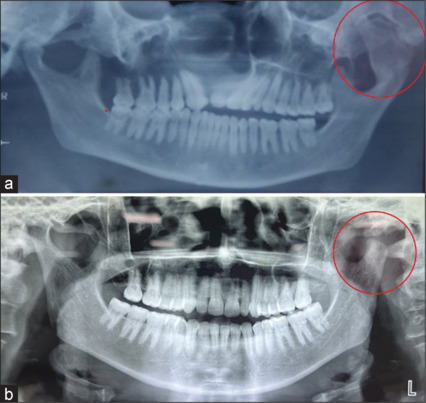

Osteochondroma is a benign bone tumor commonly found in long bones but is relatively rare in the facial skeleton, specifically the jaws. Osteochondroma in the jaws presents diagnostic challenges due to its unique location and potential involvement of dental and oral structures. Differential diagnoses include ossifying fibroma, ameloblastoma, and odontogenic tumors. Accurate diagnosis thorough clinical assessment and appropriate imaging and histopathological examination is crucial. Surgical excision remains the primary treatment, providing symptomatic relief, functional restoration, and prevention of complications. We present two cases of left condylar osteochondroma in female patients reported with pain and limited mouth opening with deranged occlusion. Increased awareness of osteochondroma in the jaws is essential for timely diagnosis and appropriate treatment. Understanding its clinical characteristics, diagnostic evaluation, and management aids in achieving optimal patient outcomes.